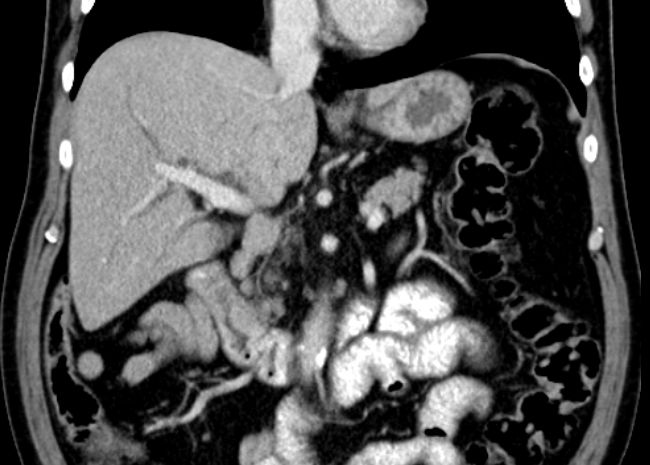

Colon 79-jährige Frau mit einem Tumor im Zoekum. Bei der Operation fand sich im Bereich der Ileozökalklappe ein unregelmäßig gestalteter, teils ulzerierter und teils polypös erhabener, 42 mm großer, derber Gewebsbezirk. Histologie: In soliden Komplexen und Strängen angeordnete, relativ große Tumorzellen mit deutlicher Zell- und Kernpolymorphie. Vergrößerte Zellkerne mit aufgelockerter Chromatinstruktur und ab und an prominenten Nukleolen. Schmaler oder kaum erkennbarer Zytoplasmasaum. Vermehrt typische und atypische Mitosen. Tumoreinbruch in Blut- und Lymphgefäße. Das CT zeigt multiple Lebermetastasen.